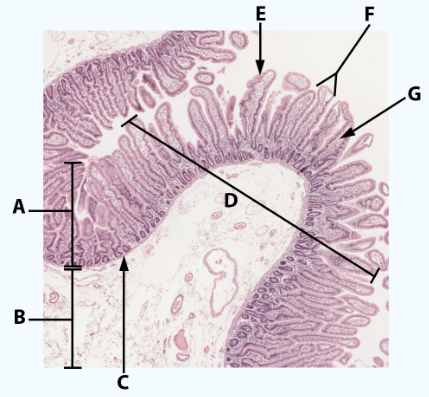

A

Mucosa: simple columnar epithelium with microvilli

B

Submucosa

C

muscularis mucosa

Area

Small intestine

E

simple columnar epithelium with goblet cells and microvilli

F

Villi

G

Lamina propria